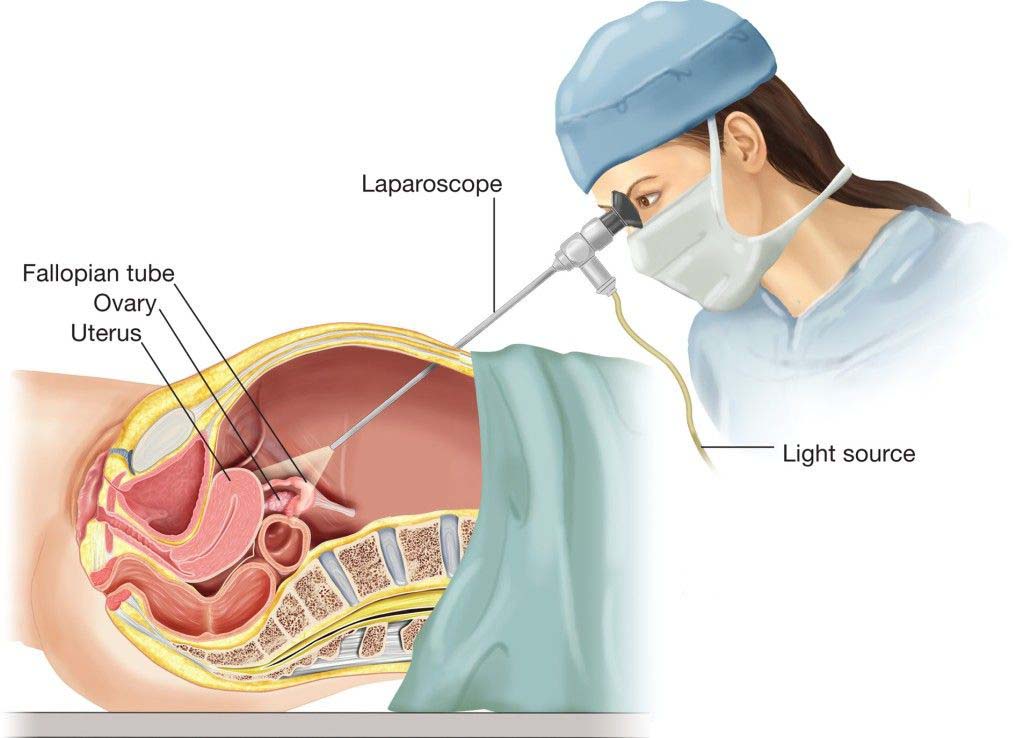

قیمت: 32٬000 تومان - دسته بندی فایل: علوم پزشکیپاورپوینت جراحی لاپاراسکوپی

فروش ویژه پاور پوینت حرفه ای جراحی لاپاراسکوپی با تخفیف استثنایی فقط 54 هزار تومان تعداد اسلاید: 21 اسلاید